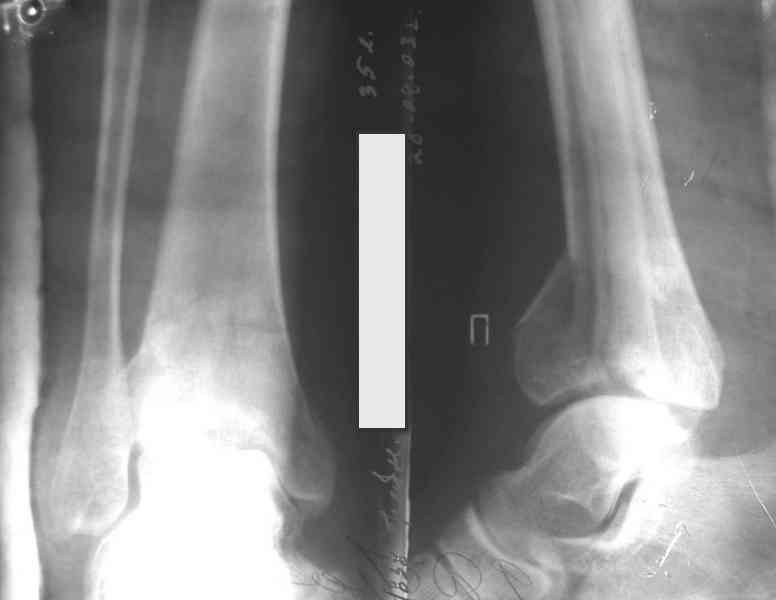

Посылаю результат лечения предыдущего больного через год.

С уважением Дрягин